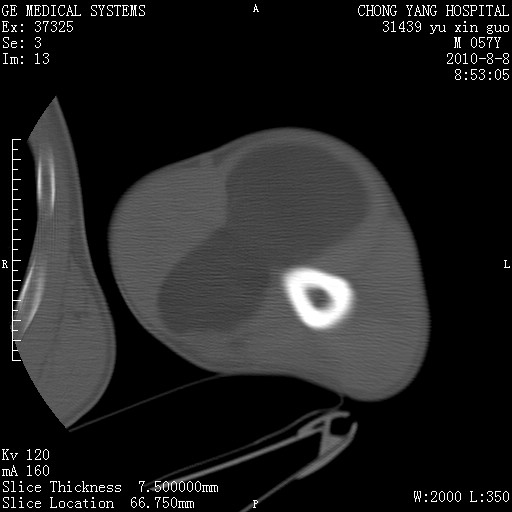

标题: CT28267:M57Y 上臂包块8年余。 [打印本页]

标题: CT28267:M57Y 上臂包块8年余。

典型脂肪瘤

包膜光滑、完整的脂肪密度肿块,支持脂肪瘤。

脂肪瘤。有ct值?